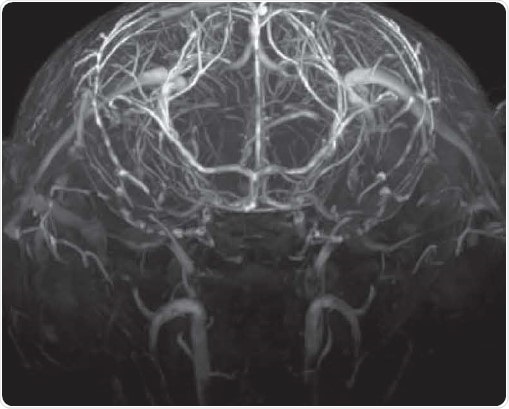

Angiography

Time-of-flight angiography with no contrast agent at high spatial resolution showing excellent contrast enabling the identification of fine vascular structures. Image Credit: Bruker BioSpin Group

"This increased SNR can be invested in either reducing the acquisition time by a factor 6.25 at constant SNR or, as in the examples shown, in enhancing image quality, i.e. increase the CNR to improve the definition of anatomical structures. and/or to increase the spatial resolution in structural imaging ad angiography.”

Prof. Dr. Markus Rudin, ETH. Zürich. Switzerland